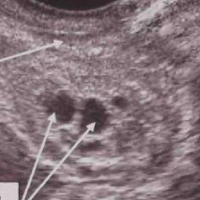

| АМГ вырабатывают фолликулы – маленькие пузырьки в яичниках, внутри которых «живут» незрелые яйцеклетки. | ![]() |

Так как АМГ вырабатывают фолликулы, его концентрация напрямую отражает их количество и активность:

![]() много фолликулов - высокий АМГ |

![]() мало фолликулов - низкий АМГ |